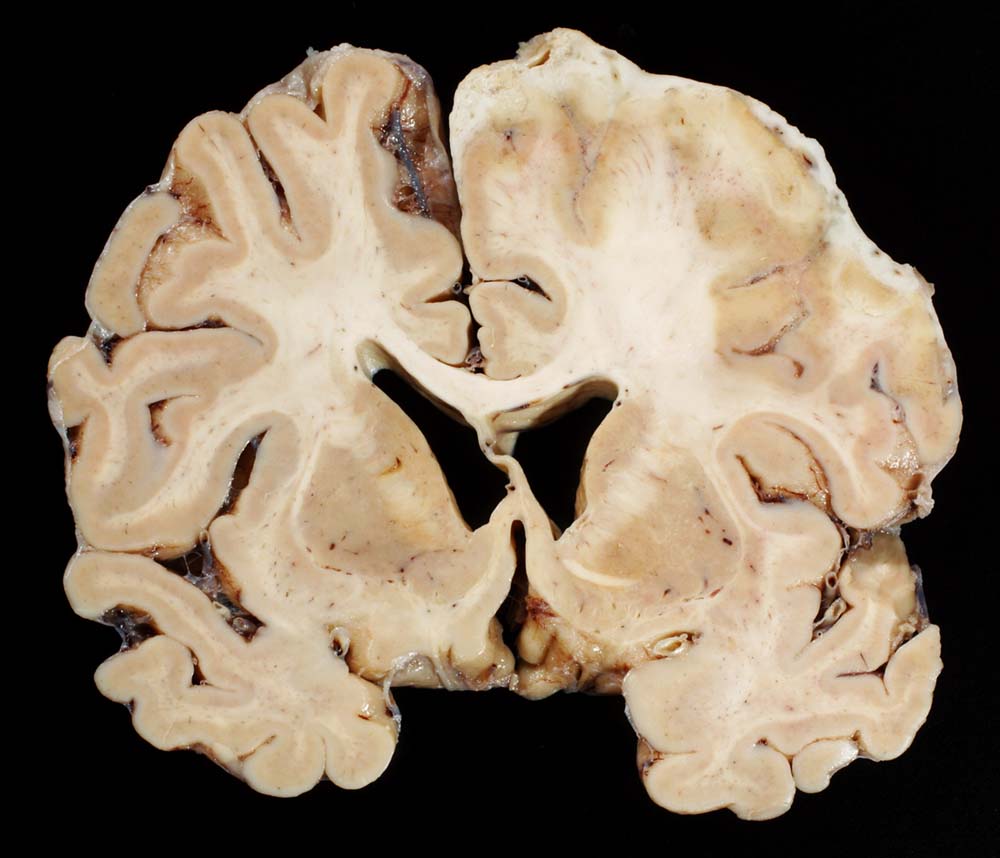

Der makroskopische Befund bei bakterieller Meningitis kann sehr diskret sein. Die meningealen Gefässe sind hyperämisch und die Hirnoberfläche wird von einem grüngelben Eiterbelag bedeckt (eher basal bei Hämophilus influenzae, eher über der Konvexität bei Pneumokokken=Haubenmeningitis). Histologisch ist der Subarachnoidalraum mit Eiter gefüllt. Bei weniger schweren Fällen finden sich die neutrophilen Granulozyten bevorzugt um die leptomeningealen Gefässe.

• Der verbreiterte Subarachnoidalraum ist mit Eiter und Ödemflüssigkeit ausgefüllt.

• Ein Teil der leptomeningealen Gefässe zeigt eine fibrinoide Nekrose der Gefässwand.

• Ein Teil der Gefässlumina angefüllt mit Fibrin und neutrophilen Granulozyten.